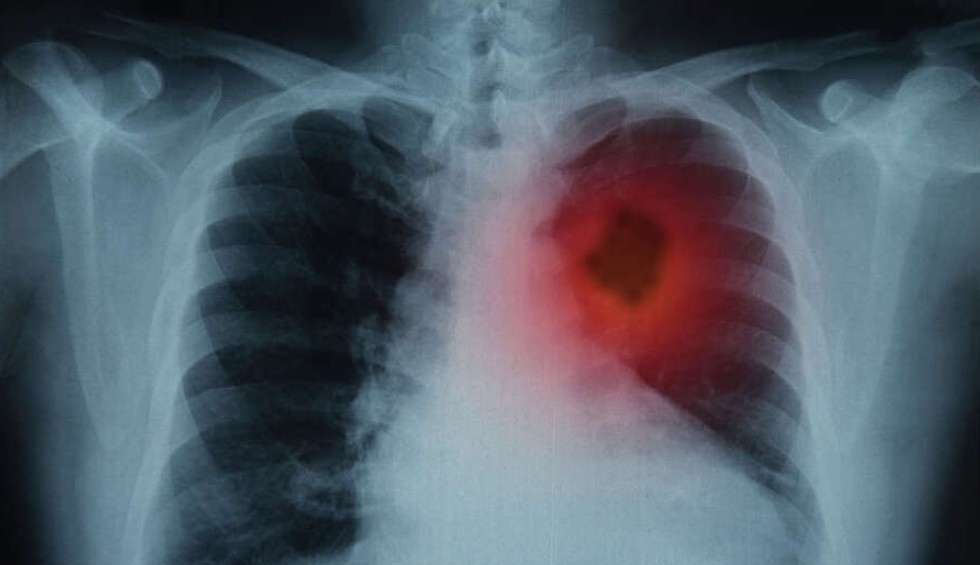

«Φρένο» στον πολλαπλασιασμό των καρκινικών κυττάρων στην περιοχή του πνεύμονα βάζει η βερβερίνη, μια φυσική ένωση που βρίσκεται σε μια ποικιλία βοτάνων όπως, ξαγκαθιά, γλυκαγκαθιά, τρικοκκιά, μπερβερίτσι, στoν θάμνο οξυάκανθα (Βερβερίς η κοινή, Berberis vulgaris, γνωστή και ως Ευρωπαϊκή οξυάκανθα) και στo βότανο υδραστίς η καναδική (Hydrastis Canadensis).

Σύμφωνα με νεότερη μελέτη που δημοσιεύτηκε στο Antioxidants, η φυσική ένωση κατέστειλλε τον πολλαπλασιασμό των καρκινικών κυττάρων του πνεύμονα στο εργαστήριο (in vitro), μειώνοντας παράλληλα τη φλεγμονή των αεραγωγών και τη βλάβη στα υγιή πνευμονικά κύτταρα που εκτίθενται σε χημικές ουσίες από τον καπνό του τσιγάρου.

Αξίζει να αναφερθεί, τέλος, ότι ο καρκίνος του πνεύμονα είναι είναι η κύρια αιτία θανάτων από καρκίνο παγκοσμίως, με περίπου 1,8 εκατομμύρια θανάτους να αναφέρονται ετησίως.